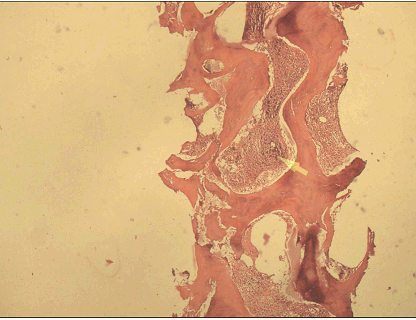

A 14-years-old female child, already a documented case of Down's syndrome proved on cytogenetic analysis, presented to our institute with fever of five days duration associated with bleeding from nose and mouth. Clinical examination of the patient revealed features of Down's syndrome like short stature, macroglossia, low set ears, simian crease and delayed milestones. Abdominal examination revealed palpable splenomegaly two cm below the costal margin. There was no hepatomegaly. Her hematological parameters showed hemoglobin of 3.2 g/dl, total leukocyte count of 3x103/mm3 with normal differential count and platelet count of 2x105/mm3. Examination of blood film did not reveal any immature cells. Erythrocyte sedimentation rate was 84 mm/1st hr. The biochemical parameters were within normal range. She was subjected to bone marrow examination. Bone marrow aspiration revealed a dry tap. Bone marrow biopsy revealed a hypocellular marrow showing presence of granulomatous inflammation consisting of epithelioid cells, Langhan's giant cells, lymphocytes and plasma cells with central areas of caseation necrosis (Figure 1, 2). Ziehl-Neelsen (ZN) staining for AFB was positive. Areas of marked fibrosis with pockets of increased number of megakaryocytes and fibroblasts were present. Reticulin stain showed increased bone marrow reticulin fibres (Figure 3), thus supporting the diagnosis of myelofibrosis. There was no evidence of any leukemic involvement. Since the patient hailed from tuberculous endemic area, diagnosis of myelofibrosis secondary to tuberculosis was contemplated. The patient was put on a course of antitubercular treatment (ATT). Unfortunately she was lost to follow up; therefore repeat bone marrow biopsy could not be done to assess the course of the disease.

Figure 1: Bone Marrow biopsy, the hematopoietic elements are replaced by granulomas and areas of fibrosis. (H&E, x400).